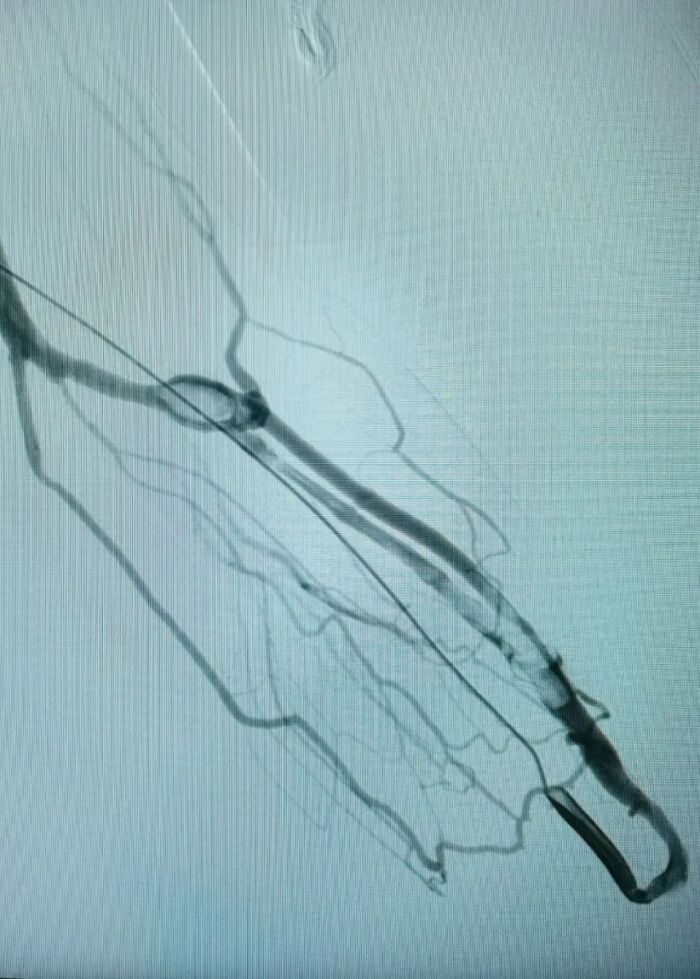

术中.jpg

术中影像

术中2.jpg术中影像